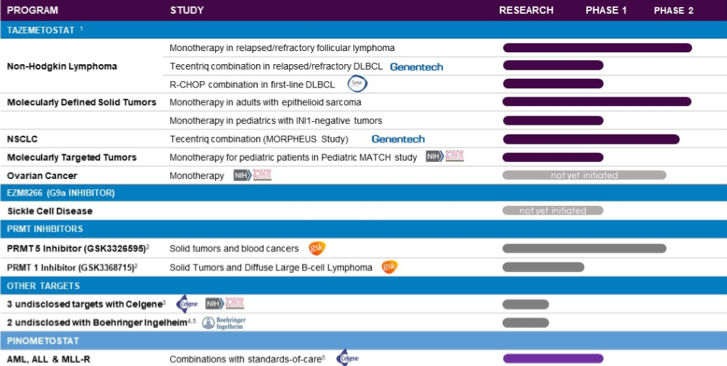

Epigenetics is at the core of its novel therapeutic inventions for treatment of cancer and other serious illnesses and the company is pioneering the development of small molecule inhibitors of histone methyltransferases (HMTs), histone acetyltransferases (HATs) and helicases. It is focused on creating oral medication that can target specific diseases and offer ease of administration and tolerability. Presently, three out of its five novel epigenetic therapies are in clinical development stage and two are in pre-clinical stage.

Its lead drug candidate, tazemetostat, is being developed for the treatment of cancer using its platform of new epigenetic target classes that are crucial in disease biology. Its line-up of clinical candidates consists of novel small molecule programs for new disease targets such as EZM8266, a potential treatment of sickle-cell disease.

Image Source: http://www.epizyme.com/programs/product-platform/

Epizyme has entered into key strategic collaborations with companies such as Boehringer Ingelheim, Genentech (a member of the Roche Group), Lymphoma Study Association (LYSA), EISAI Co. Ltd. (TYO:4523), Celgene Corporation (NASDAQ:CELG) and GlaxoSmithKline plc (NYSE:GSK) for advancing the development of its drug candidates as well as leveraging on a range of research and development programs. It has received over $200 million in non-equity funding till date due to these agreements. As part of its arrangements with EISAI, it has retained the global rights to tazemetostat, an EZH2 inhibitor outside of Japan for an upfront payment of $40 million and consideration of future royalties, while with Celgene it has commercialization rights in the United States for two of their programs namely DOT1L (Acute leukemia) and pinometostat (EPZ-5676) for $65 million in upfront payment and an equity investment of an additional $25 million besides royalty and milestone payments in the future.

It’s collaboration with Boehringer Ingelheim is for enzymes within the helicase and histone acetyltransferase (HAT) families whose dysfunction has been linked to the development of cancers. Genetech and Epizye have an agreement to study the combination of tazemetostat and Genentech’s approved anti-PD-L1 cancer immunotherapy, Tecentriq™ (atezolizumab), for the treatment of patients with relapsed or refractory diffuse large B-cell lymphoma (DLBCL), the most common form of non-Hodgkin lymphoma (NHL).

LYSA and its collaboration are for the investigation of its tazemetostat with R-CHOP, a standard chemotherapy for NHL, as a front-line treatment in elderly, high-risk patients with newly diagnosed DLBCL. GSK paid an upfront payment of $20 million with research, development and regulatory milestone payments of up to $402 million and sales-based milestone payments of up to $218 million in the offing for its novel small molecule HMT inhibitors.